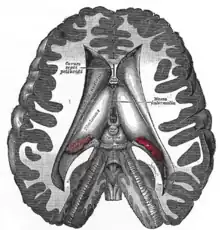

Vue médiale d'une dissection profonde montrant la face médiale de l'hémisphère cérébral.